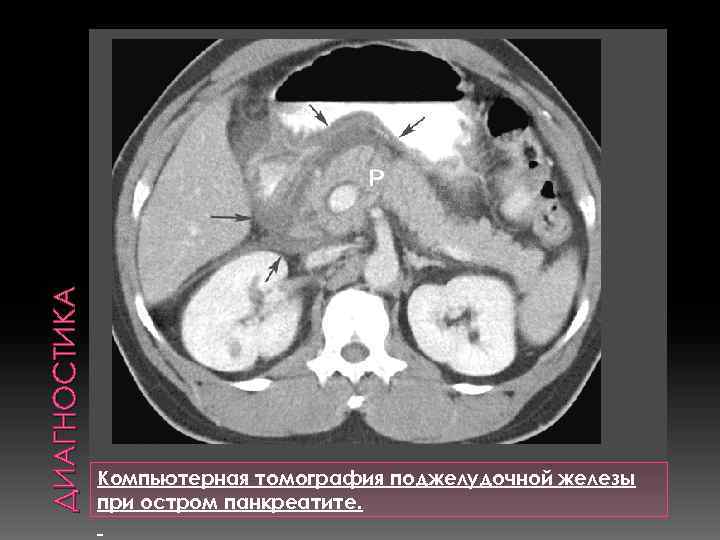

ДИАГНОСТИКА Компьютерная томография поджелудочной железы при остром панкреатите.

ДИАГНОСТИКА Компьютерная томография поджелудочной железы при остром панкреатите.